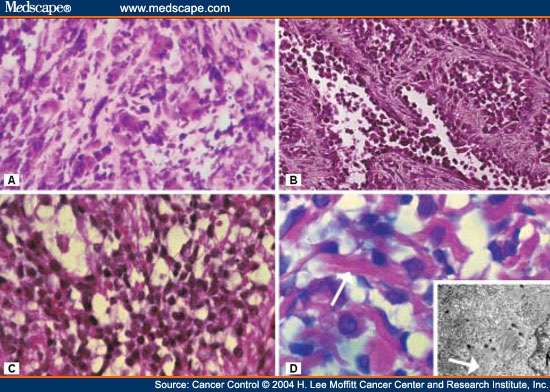

Orbital Rhabdomyosarcoma - Page 2

www.medscape.com

www.medscape.com

rhabdomyosarcoma orbital figure